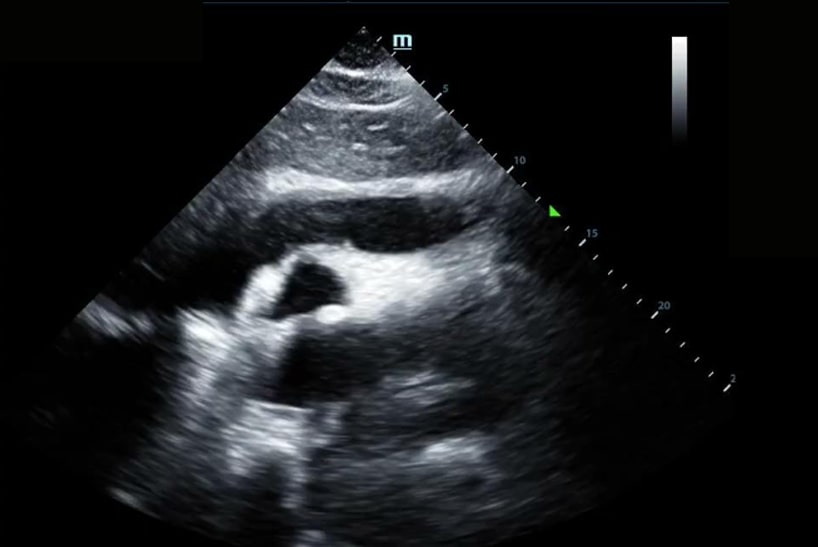

When asked to lie flat for the cardiac exam, he noted worsening chest discomfort. Upon obtaining the initial Parasternal Long Axis (PLAX) view, all eyes in the room grew wide in surprise.

Here you can see a significant pericardial effusion in PLAX and Subxiphoid views with concerns for early tamponade. This was communicated with the cardiology team who promptly drained 400cc of serosanguinous fluid. Ultimately there was no obvious source for this effusion. Since this experience, I always make sure to take at least a quick peek at the heart in respiratory cases where lung ultrasound is unrevealing.